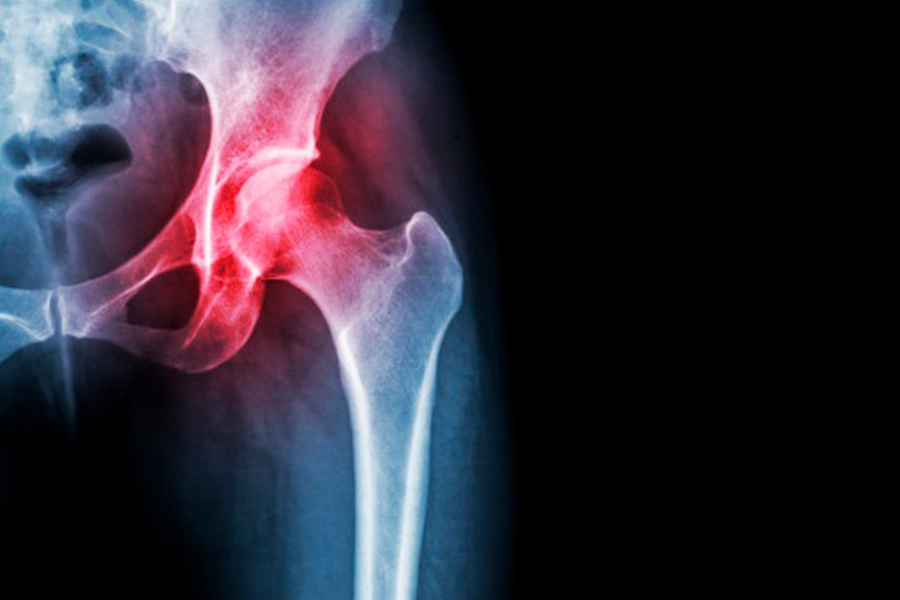

Si la movilidad de la cadera se restringe cada vez más dolorosamente, la causa suele ser una artrosis de cadera: la artrosis es el desgaste creciente del cartílago articular, que afecta gradualmente a los huesos, así como a la función de tendones, ligamentos y músculos.

El movimiento en la articulación de la cadera se vuelve cada vez más doloroso para los pacientes afectados. La articulación de la cadera también puede perder su forma. La articulación se puso rígida.

En la etapa II de la osteoartritis de cadera, el paciente ya tiene dolor de cadera como un dolor inicial o como un bloqueo doloroso del movimiento con ciertos movimientos. Los llamados espolones óseos (osteofitos) se forman dondequiera que los huesos de la osteoartritis de la cadera, ya sea por pinzamiento de la cadera o después de que el cartílago se desgaste, toque y colisione.

Con cada movimiento, estos osteofitos en la articulación de la cadera se colocan sobre la capa opuesta de cartílago en la articulación de la cadera. En algún momento, los huesos de las articulaciones involucradas se frotan entre sí.

Hacen que las superficies de las articulaciones sean ásperas y aceleran significativamente el desgaste del cartílago en la cadera.

La capa de cartílago sirve como capa deslizante y amortiguador. El cartílago mantiene todas las articulaciones flexibles. En el caso de la osteoartritis, esta capa deslizante en la articulación inicialmente se vuelve áspera y agrietada, luego más delgada y más delgada y erosionada.

Si el cartílago se desgasta y los huesos se rozan entre sí (los llamados huesos calvos), también se atacan los huesos, ligamentos y cápsulas articulares de la articulación de la cadera.